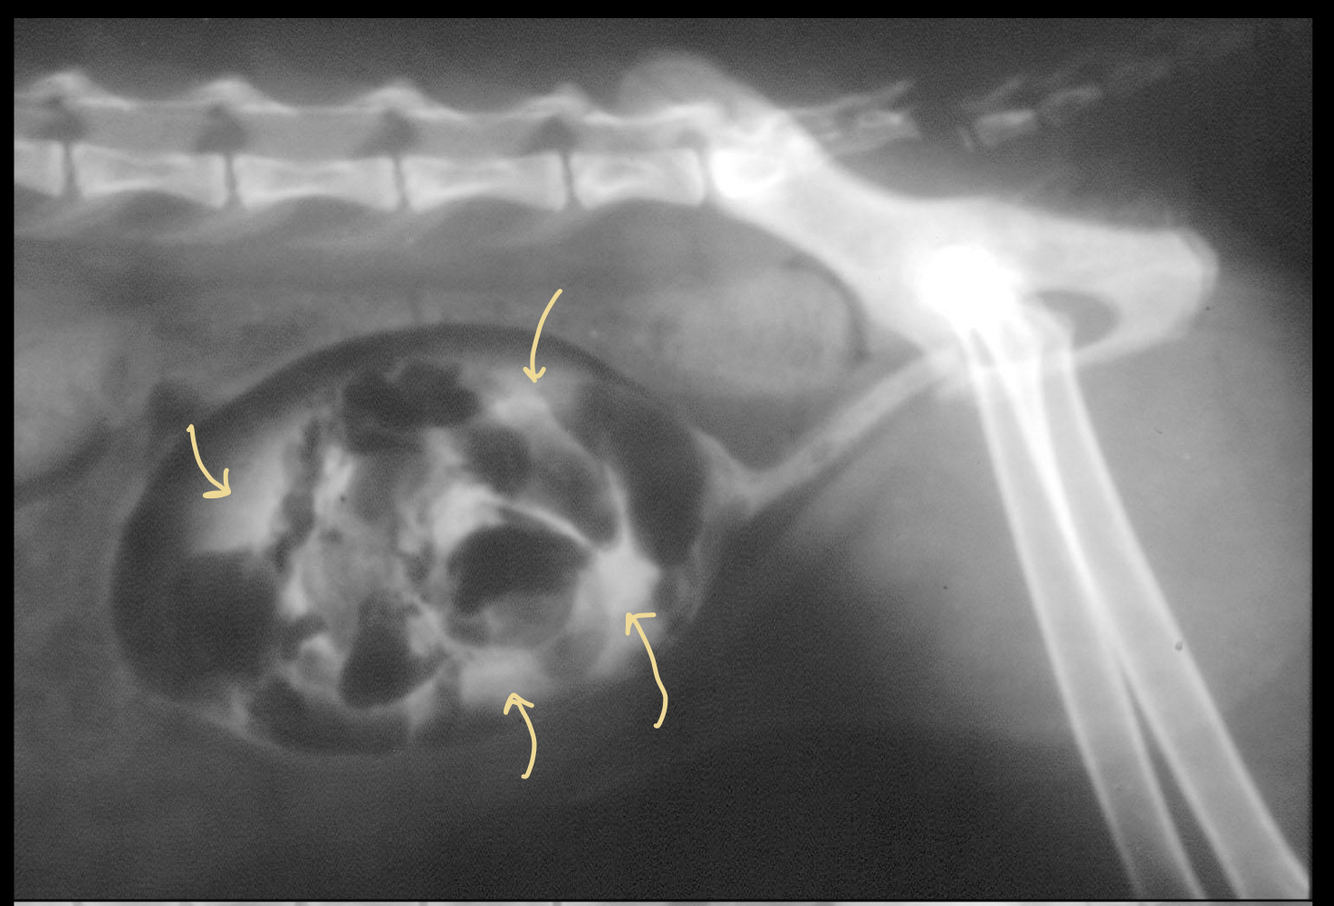

Q

What is being pointed to in this cystourethrograph?

A

negative gas contrast

positive iodine contrast